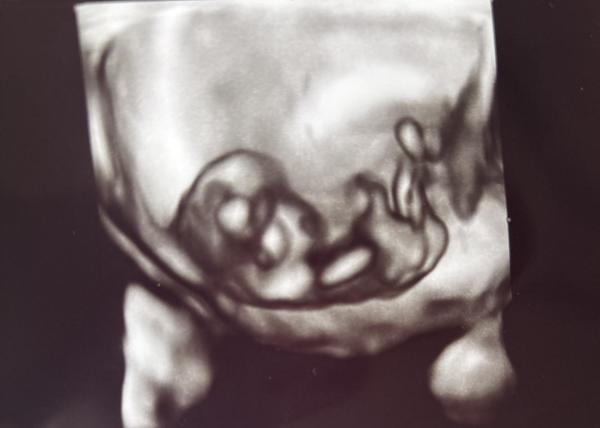

Hey kennt sich jemand mit NUB oder Ramzi aus? Es ist mein 2. Kind und ich wusste bei dem ersten oh das wird ein Junge, habe mich von meinem Mann überzeugen lassen es wird ein Mädchen tatdaaaa es wurde ein Junge & Als ich den Test gemacht habe und den 2. Strich gesehen habe dachte ich direkt ohhhh ich kann Kleidchen kaufen jetzt meine Frage was denkt ihr welches Geschlecht es ist? 1. Bild SSW 7+4 2. + 3. Bild SSW 10+5

Bild zu NUB oder Ramzi - Forum für Juni - Mamis